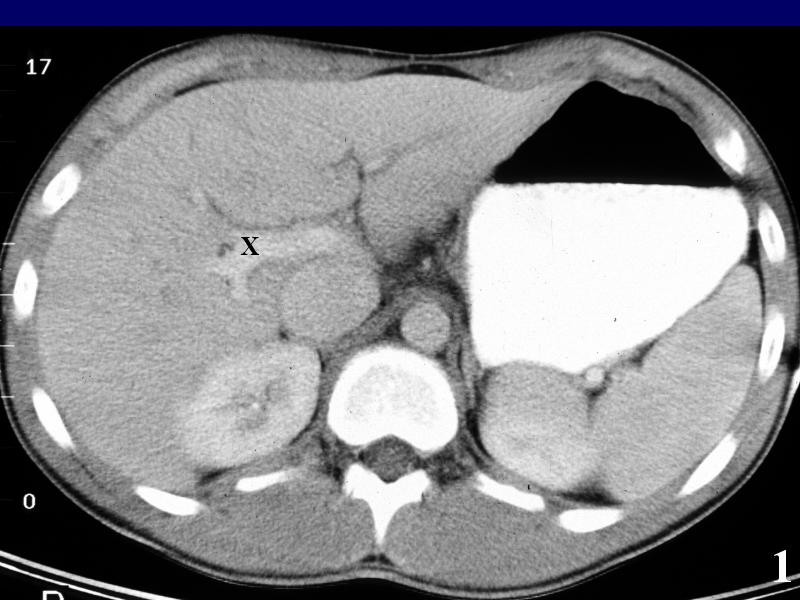

MS 190 CT 12